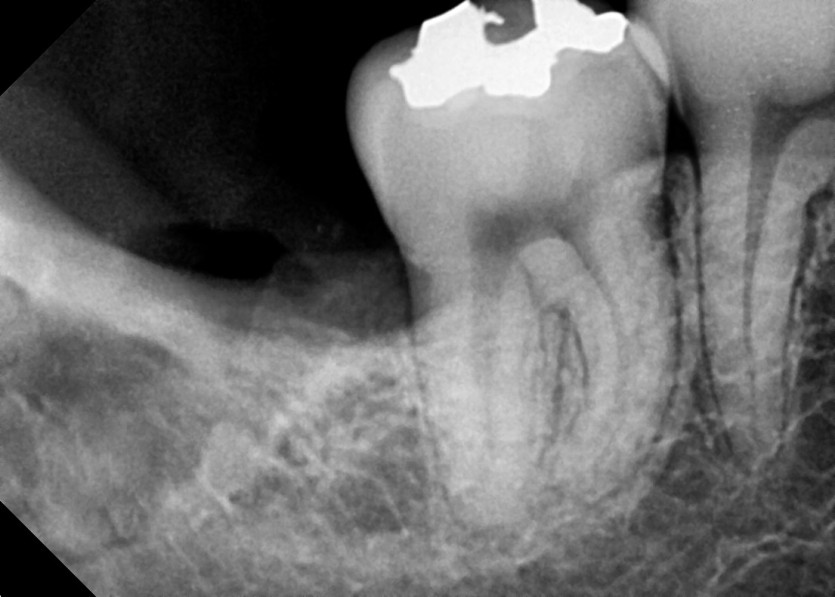

#18,48 사랑니 발치

구강 외과 전문의가 당일 발치했습니다.